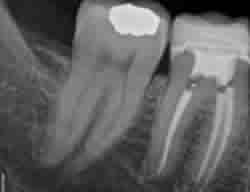

Root Canal Therapy allows us to save your tooth rather than you requiring more costly procedures such as an implant or denture. The process involves creating an opening in the crown of your tooth. The pulp in the 'root canal' is completely removed and the 'canal' is cleaned out, shaped and smoothed. Any infection (we refer to as abscess) is treated and the bacteria that cause it are cleaned out.

The canal area, once infection free is filled and sealed. As the tooth will no longer be receiving vital nutrients it will be more brittle than surrounding teeth. For this reason we create a Crown or Cap to strengthen and protect your tooth's chewing surface, especially if it was one of your back teeth. Once ready the Crown is cemented in place and 'your tooth' rather than an artificial replacement keeps its place in your smile.